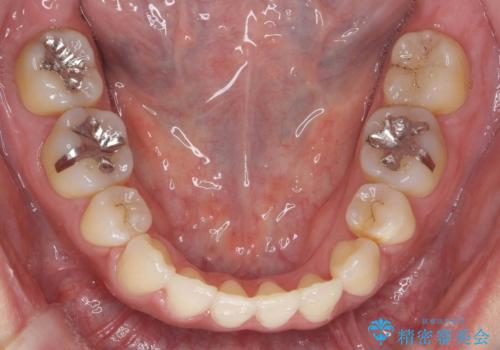

真ん中が右にずれている 前歯のがたつき 治療途中に地方へ引っ越したが、通ってワイヤー矯正

- 前歯のがたつきを主訴に来院。

前歯のクロスバイト、上の前歯の正中が右にずれていました。

右上の奥歯の高さもない状態でしたが、矯正治療が終わってからしっかりかぶせました。

上下左右の小臼歯を抜歯しています。